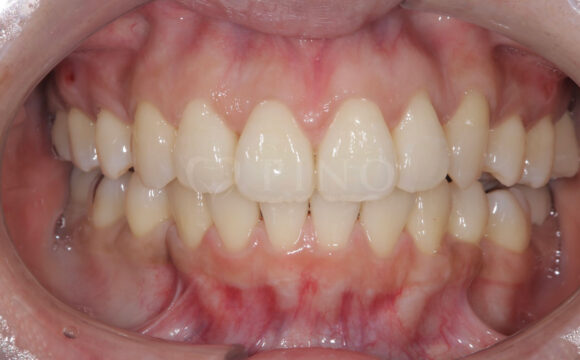

症例3:ワイヤー矯正後の後戻りが気になる(40代女性)

主訴 ワイヤー矯正後の後戻りが気になる 診断名 叢生 治療方法 マウスピース部分矯正 抜歯 なし オルソパルス なし 治療期間 9ヶ月 費用 436,000円 副作用・注意点 矯正後の後戻りを防ぐためリテーナーの使用が必要となる 備考 奥歯に噛み合わせ不良がない場合、部分矯正が適応となる -